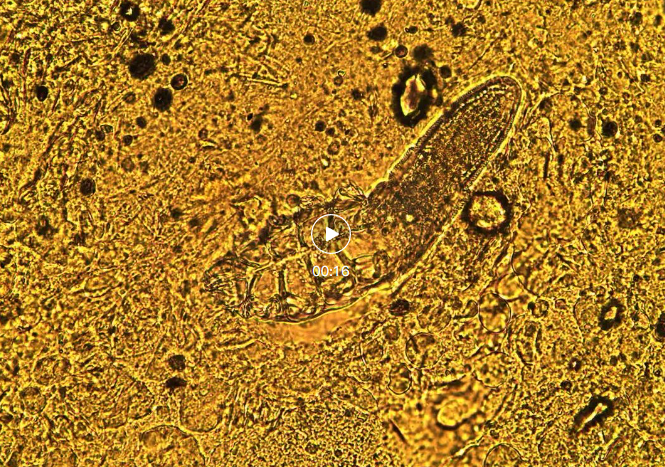

OMG,我的天哪,这是什么? 没错这就是从王女士脸上刮下的“小宝贝”。